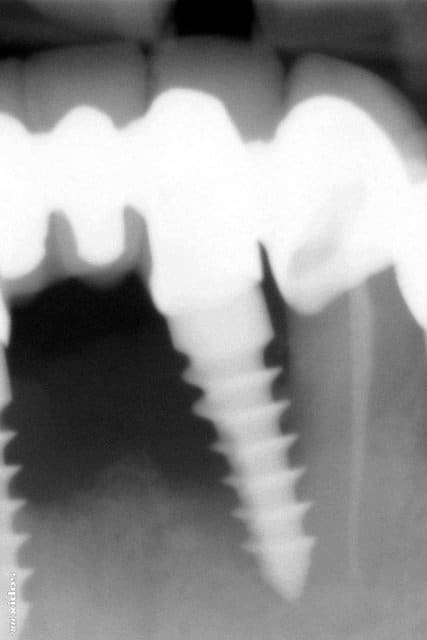

Je vous joins une panoramique, j'ai dû faire une capture d'écran, j'espère que c'est lisible.

Patient la cinquantaine, pas d'ATCD médicaux, fumeur occasionnel, motivé, du tartre en pagaïe.

Reconstruction par deux bridges complets, dento-implanto-portés, effectuée de l'autre côté de la frontière par praticiens français.

Le travail a environ 18 mois sur cette radio.

Je connais pas grand chose en implantologie.. mais il me semble que , ici, il y a TOUT ce qu'il ne faut SURTOUT pas faire, non ?

Implant mal enfoui, limite cervicale anti-anatomique

Hybride dent naturels/implant, à éviter à tout prix.

Implant trop prêt de la racine d'une dent naturelle.

Notions d'hygiène absentes.

autres..

perte du capital osseux et financier